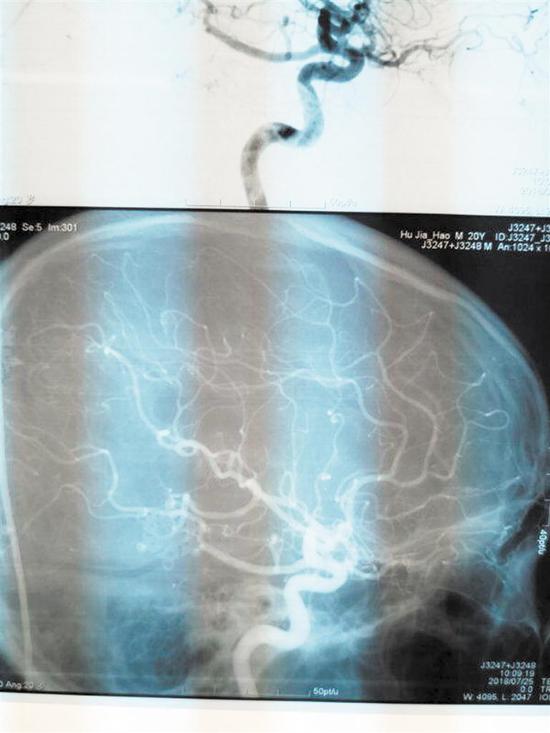

为了随时观察小陈的情况,陈淳一直在NICU守护着。“此手术为神经外科4级手术,致残率、死亡率高。手术后我们一直担心会有如瘫痪、失明等后遗症出现,幸运的是,小陈第二天就苏醒了,神志清醒,无后遗症出现。复查DSA,他的畸形血管团全切,恢复情况良好。”陈淳说。